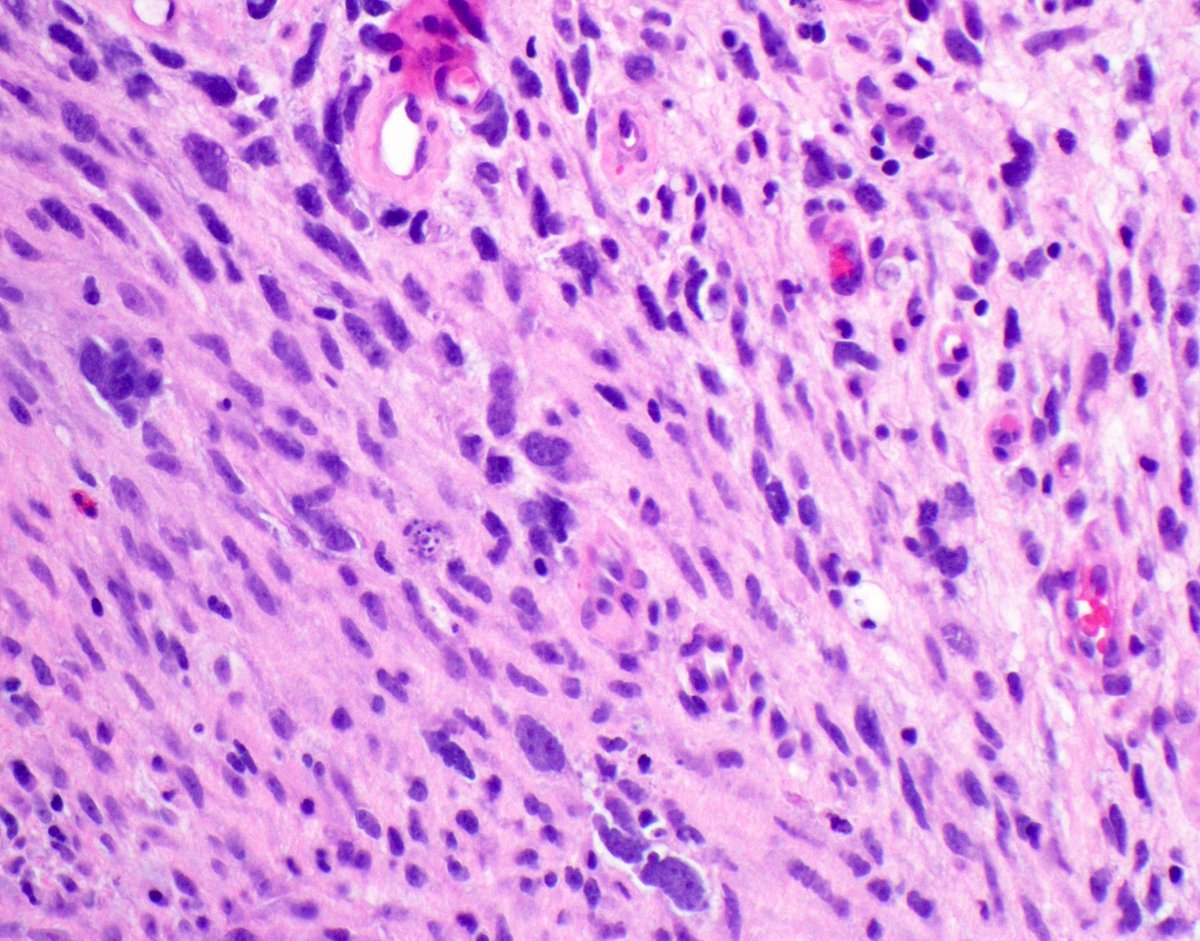

A slow-growing soft tissue mass in a child; histology shows distinctive findings and MUC4 IHC is +. Likely diagnosis? diagnostic gene fusion? #pedipath #softtissuepath #molecpath 🤔🔬🧬